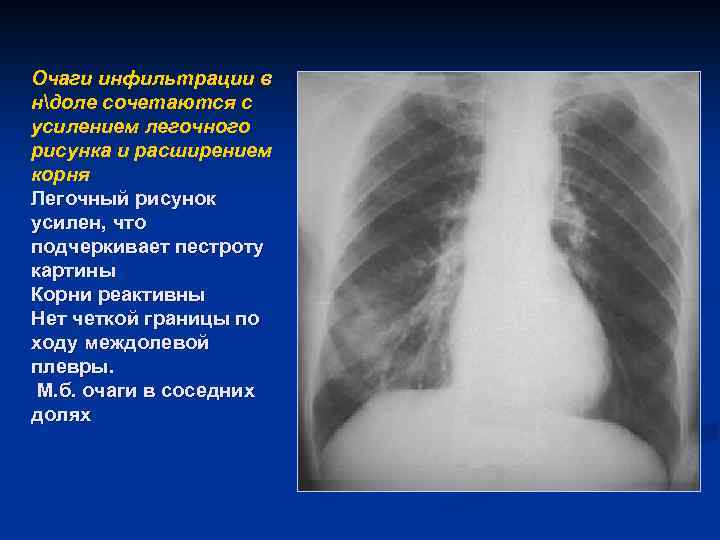

Очаги инфильтрации в ндоле сочетаются с усилением легочного рисунка и расширением корня Легочный рисунок усилен, что подчеркивает пестроту картины Корни реактивны Нет четкой границы по ходу междолевой плевры. М. б. очаги в соседних долях